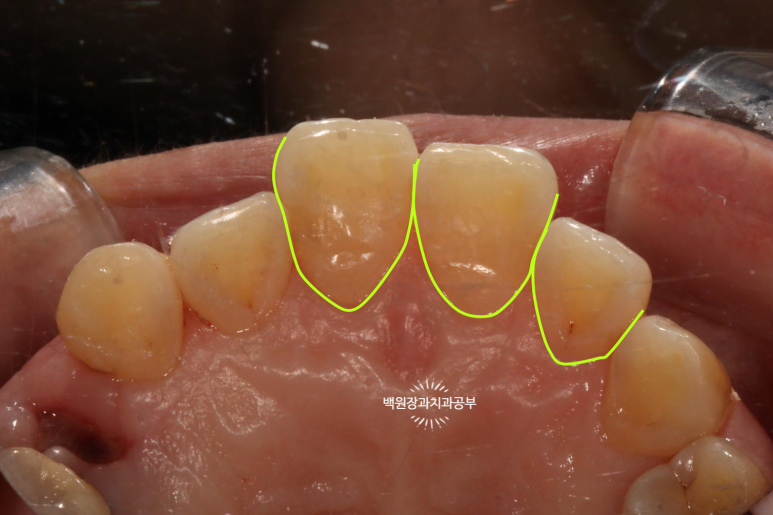

제가 보기 쉽게 표시해 드릴께요!!

노란색으로 표시해 놓은 곳들이 옆면 충치가 있는 곳들이에요!

눈으로 확인하는 시진과 방사선 검사를 종합해서 합집합이 되는 부위를 모두 치료하면 됩니다.

치료 전과 치료 후를 쉽게 비교하실 수 있도록, 치료 직전 찍어놓은 사진이에요.

상악 중절치와 측절치 그리고 견치에 옆면 모두에 충치가 있습니다.